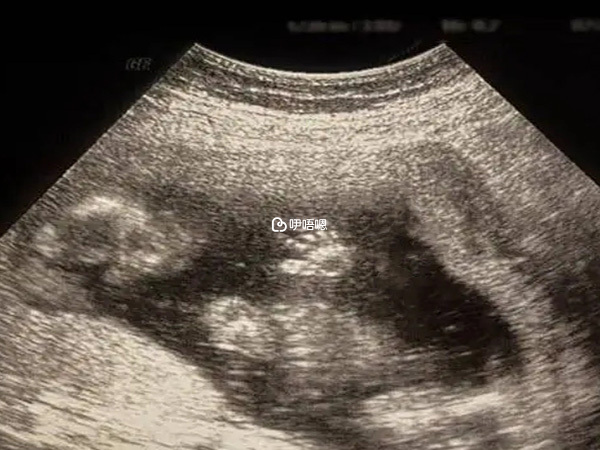

我測7月5號排卵,從那天開始完全是賭的方式,每天打針,7月16測出淺粉色雙槓,7月18開始上海之行抽血看HCG翻倍,從188隔天360多,再800左右,一直是醫生嘴裡的正常水平,我每天的基礎體溫仍然在測,擔心和從前一樣。每天如魔怔一般眼還沒有睜就開始測,有時候測著睡著了,由於是電子的,她會響,睡醒了再測,就這樣一直測到9月6號,一超二超都做完了才不測了,等待一超的過程我想過來人都知道。

從B超前的忐忑到結束後的舒暢,看著那薄薄的一張紙,寫著可見胚芽見心管搏動,還有那看不懂的黑白圖片簡直是世上最美的圖畫,就這樣醫生一次次的調整用藥到9月15日的NT,我成功啦。